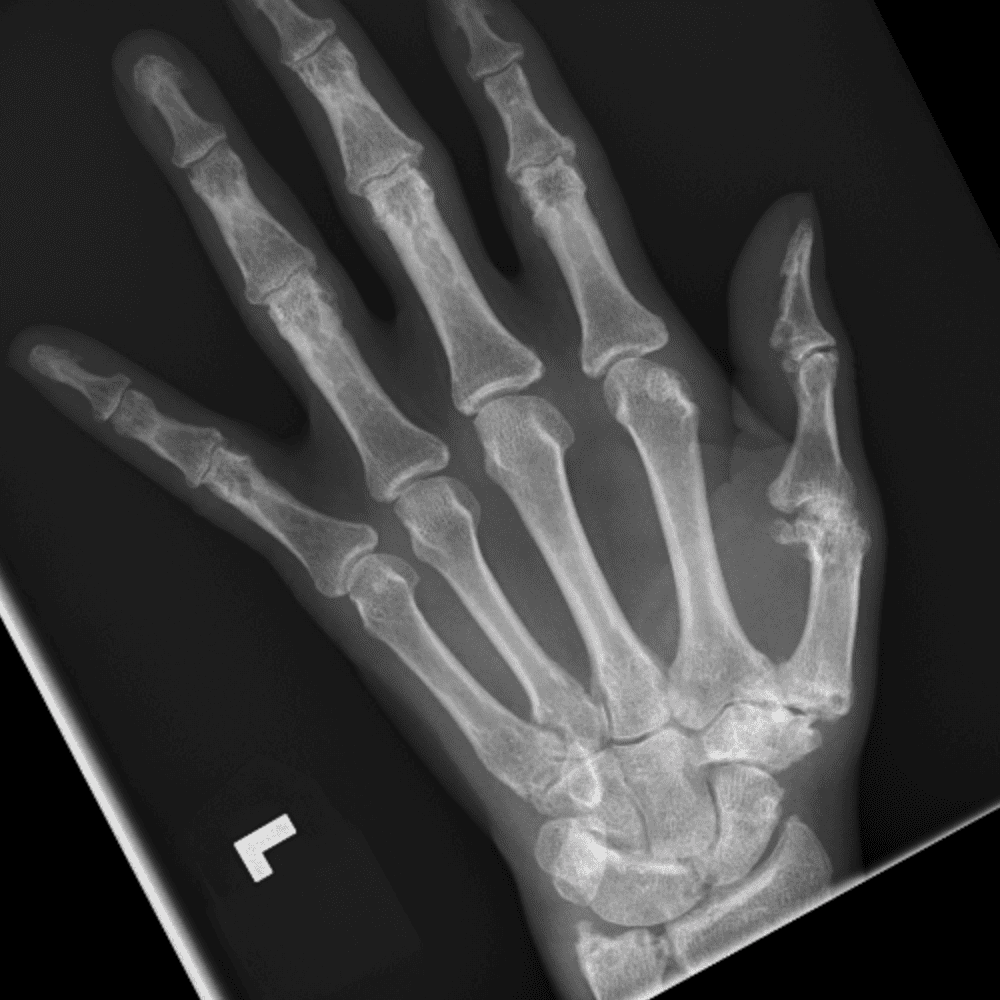

Simuliert den Dienst durch subtile oder schwierige Fälle und einige Normalbefunde.

30 Fälle